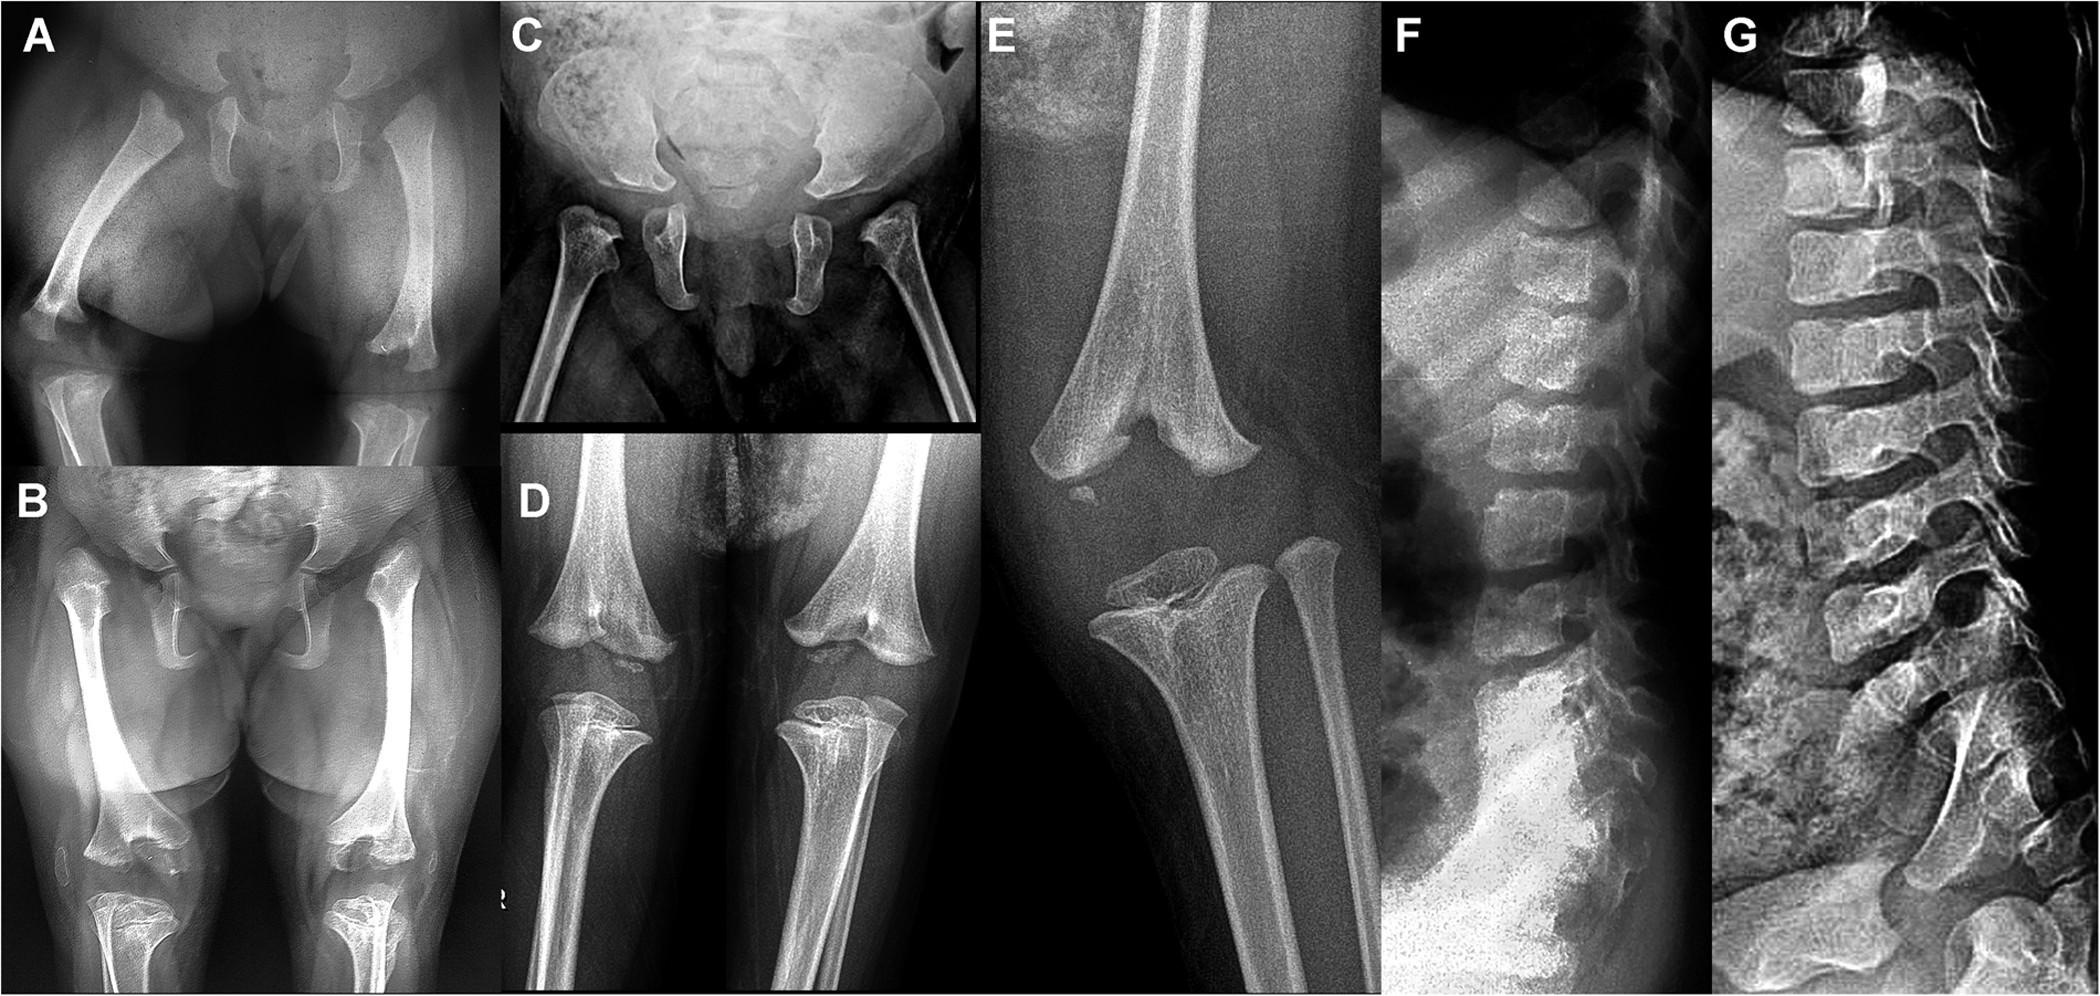

Figure 2

Skeletal-radiographic features.

Panels A and B: patient 2 at birth (A) and at age 5 years (B) showing underossified pubic bones; bilateral dysplasia of the femoral heads at birth resulting in hip dislocation at age 5 yrs; and a “bifid” appearance of the distal femur with epiphyseal delay at birth, with dysplastic epiphyses that are “socketed” in the bifid femur at age 5 yrs; and small, laterally dislocated patellae. Panels C, D and E: Patient 1 at birth (C) with dysplastic femoral heads and at age 4 years (D,E) showing the bifid distal femur and the markedly dysplastic distal femoral epiphyses. The proximal tibial epiphyses are too small but less severely affected. Panels F and G: lateral lumbar spine of patient 3 at age 3 yrs (F) and of patient 1 at age 4 yrs (G) showing remnants of coronal clefts of the vertebral bodies. The clefts are prominent at birth and gradually disappear as ossification progresses.